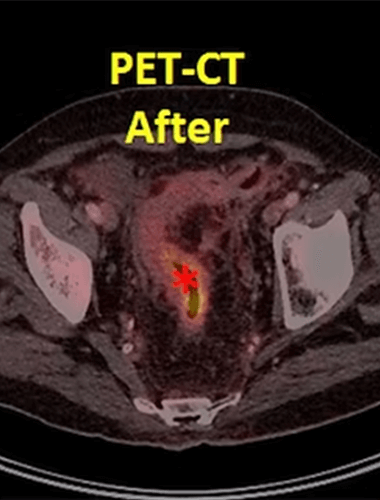

Our patient had rectal cancer (*) on PET-CT and underwent 3 sessions of intraarterial chemotherapy via the feeding artery. The control PET-CT showed that the tumor (*) has almost disappeared. The patient was operated and the specimen showed no viable tumor cells in the rectum (complete pathologic response).